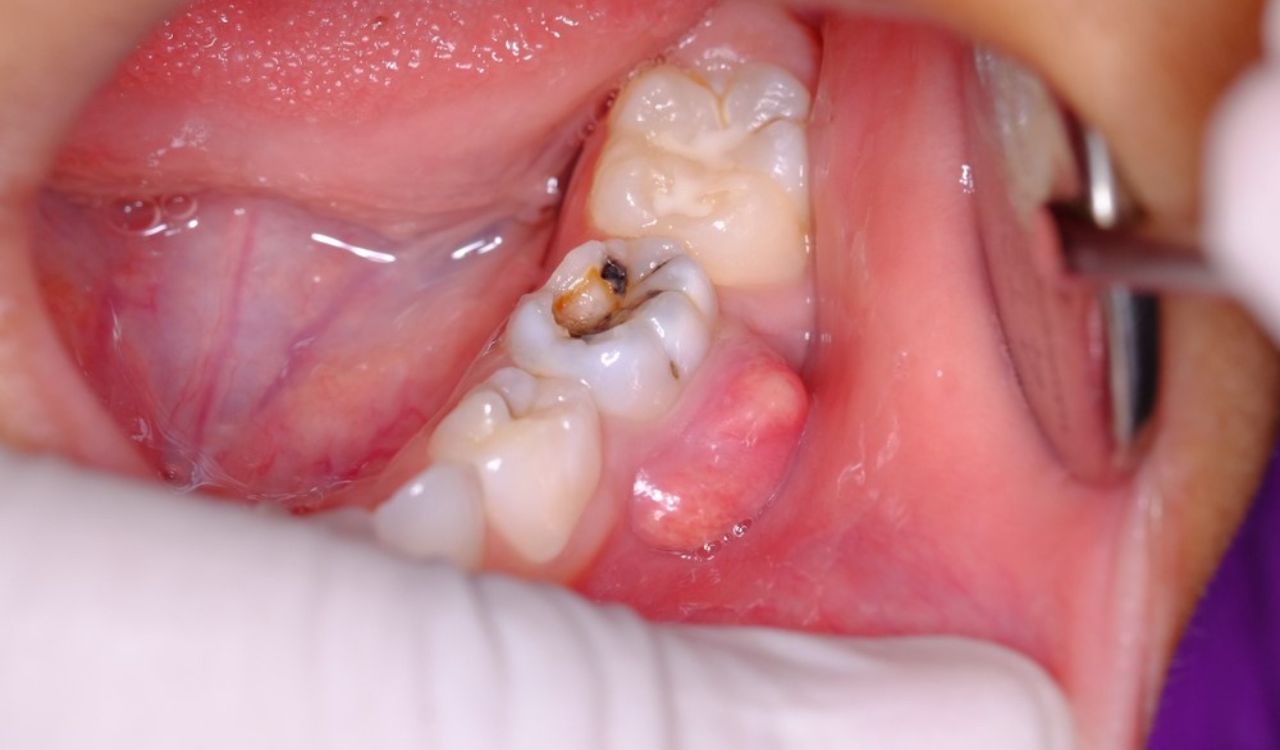

Nhóm nhiễm khuẩn miệng cấp tính và các ổ áp xe quanh chóp

Nhiễm khuẩn miệng cấp tính bao gồm các tình trạng như áp xe răng, viêm quanh cuống răng hoặc các vết loét niêm mạc miệng diện rộng. Ổ viêm cấp tính nếu kết hợp với lực chỉnh nha sẽ gây đau đớn dữ dội cho khách hàng. Việc gắn khí cụ trong môi trường đang có ổ áp xe làm tăng nguy cơ vi khuẩn xâm nhập vào máu, gây nhiễm trùng toàn thân cực kỳ nguy hiểm.

Người đang có nhiễm khuẩn trong miệng cũng thuộc nhóm những người không nên niềng răng

Giải pháp bắt buộc là loại bỏ triệt để các ổ nhiễm khuẩn bằng cách điều rạch thoát mủ áp xe hoặc sử dụng kháng sinh liều cao theo chỉ định. Chỉ sau khi các triệu chứng sưng, nóng, đỏ, đau biến mất hoàn toàn và hình ảnh X-quang cho thấy vùng xương quanh chóp răng đang có dấu hiệu lành thương, bác sĩ mới tiến hành các bước chỉnh nha đầu tiên. Việc nóng vội trong giai đoạn này không chỉ làm hỏng răng mà còn đe dọa trực tiếp đến sức khỏe tổng quát của khách hàng.